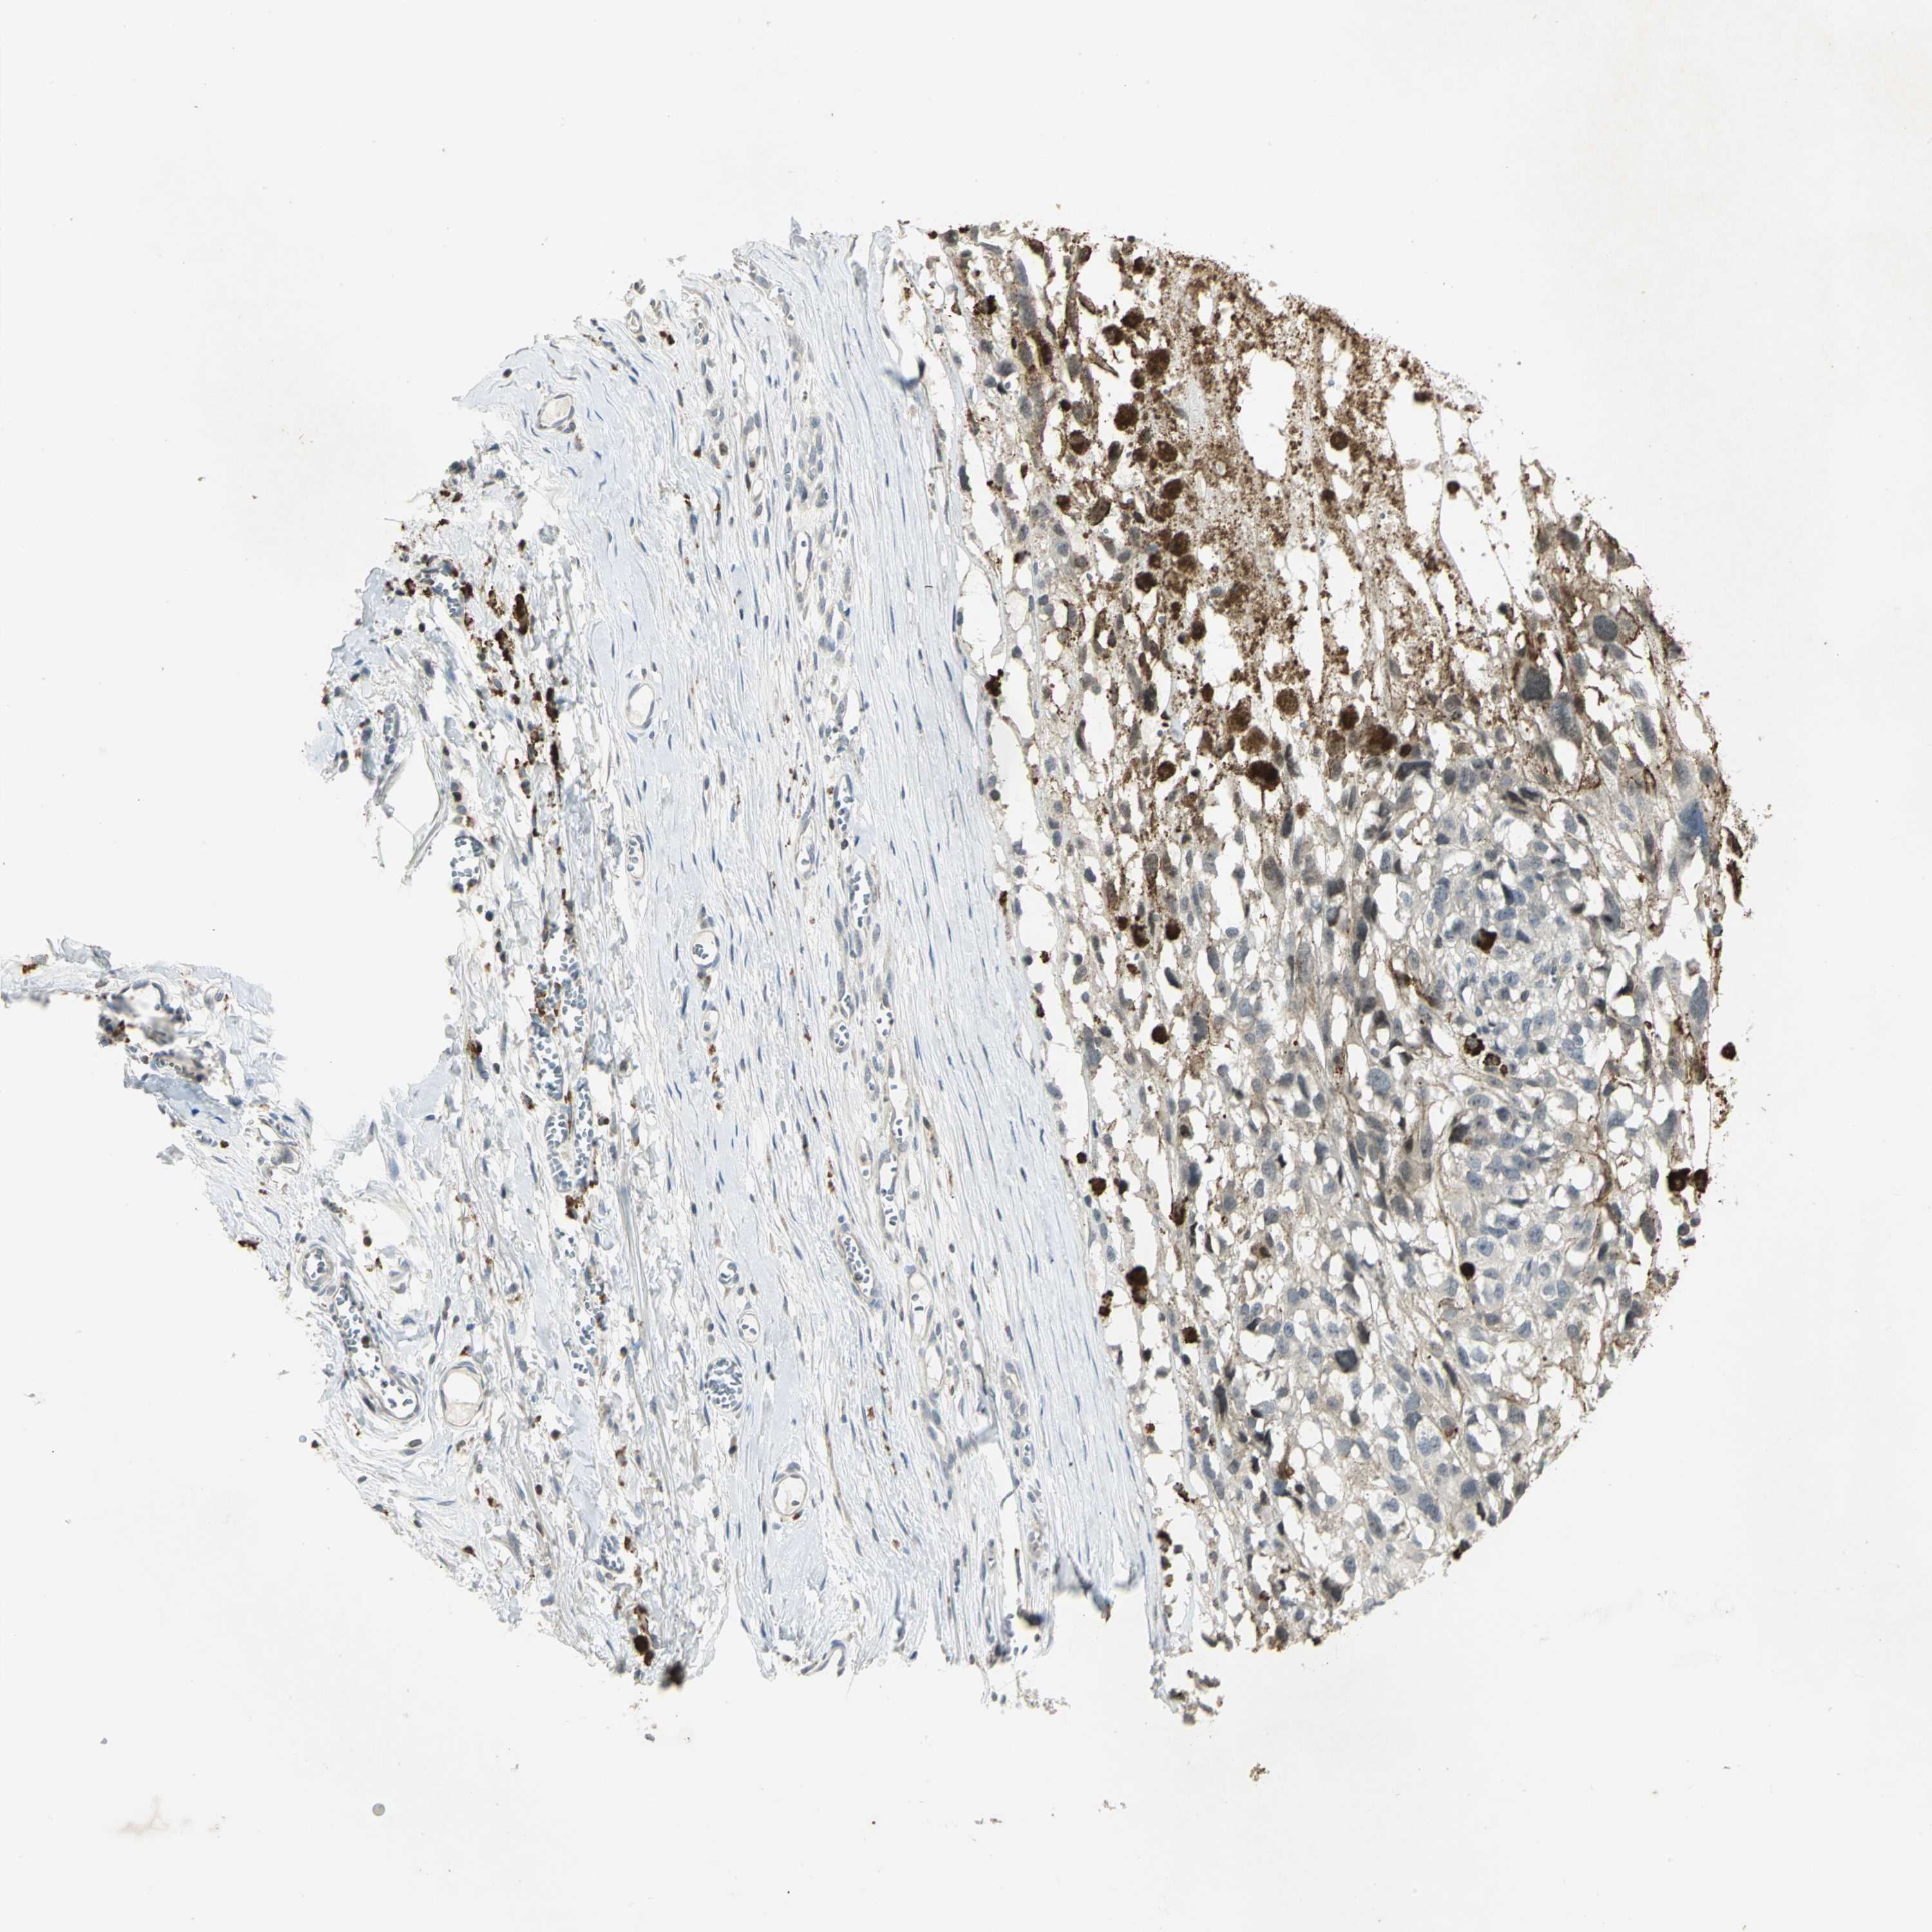

MELANOMA - Protein expressioni

A mouse-over function shows sample information and annotation data. Click on an image to view it in a full screen mode. Samples can be filtered based on level of antibody staining by selecting one or several of the following categories: high, medium, low and not detected. The assay and annotation is described here.

Note that samples used for immunohistochemistry by the Human Protein Atlas do not correspond to samples in the TCGA dataset.

Antibody stainingi

Antibody staining in the annotated cell types in the current human tissue is reported as not detected, low, medium, or high, based on conventional immunohistochemistry profiling in selected tissues. This score is based on the combination of the staining intensity and fraction of stained cells.

Each image is clickable and will lead to virtual microscopy that enables deeper exploration of all samples and also displays staining intensity scores, fraction scores and subcellular localization as well as patient and tissue information for each sample.

Antibody HPA018467

Antibody CAB005247

Staining

High

Medium

Low

Not detected

Intensity

Strong

Moderate

Weak

Negative

Quantity

>75%

75%-25%

<25%

None

Location

Nuclear

Cytoplasmic/membranous

Cytoplasmic/membranous,nuclear

Malignant melanoma, NOS

Malignant melanoma, Metastatic site